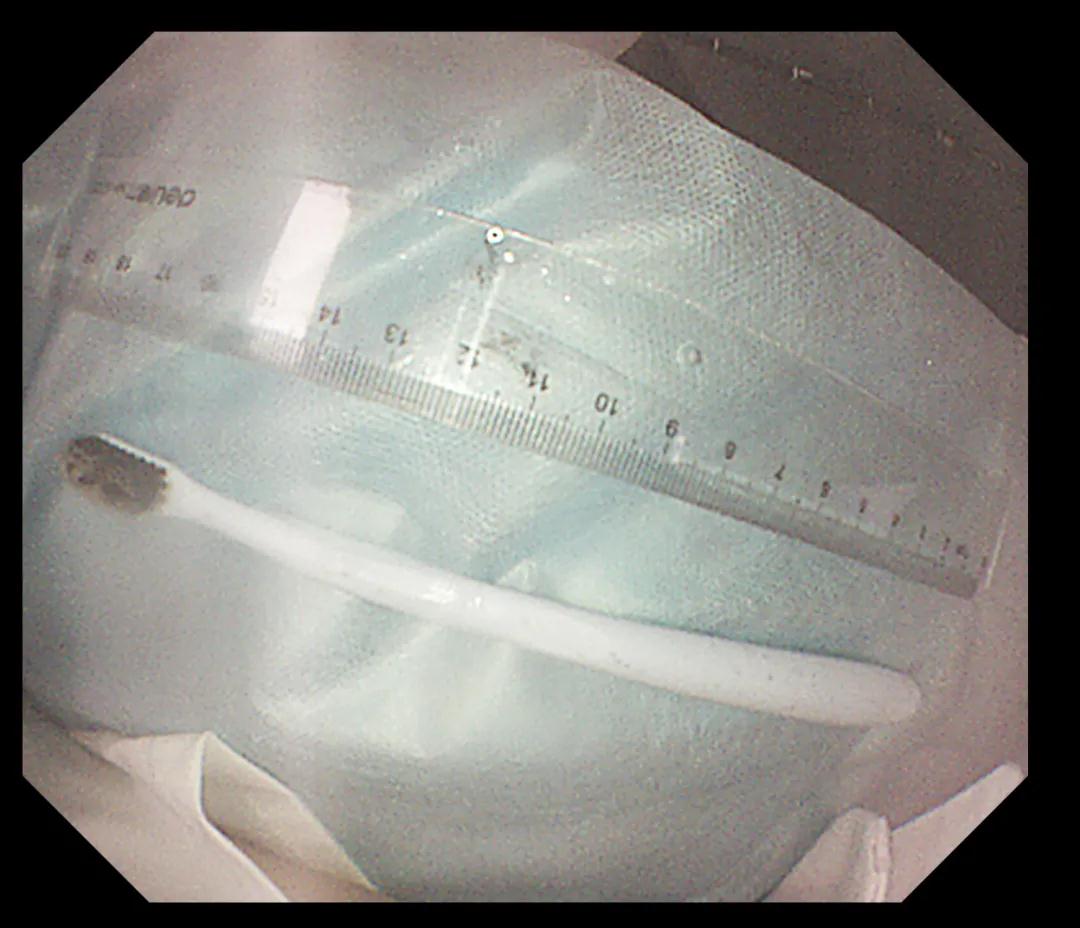

經(jīng)過(guò)反復(fù)努力嘗試,圈套器終于緊緊的套住異物,使牙刷長(zhǎng)軸盡量與食道長(zhǎng)軸平行,適當(dāng)注氣擴(kuò)張食道腔。經(jīng)過(guò)不懈努力,順利將其取出,取出牙刷經(jīng)測(cè)量長(zhǎng)度約20cm,似乎這條細(xì)細(xì)的胃鏡就是一條連接希望的生命線。此時(shí)在場(chǎng)所有人懸著的那顆心也終于落下。術(shù)后小楊癥狀逐漸消失,生命指征平穩(wěn),情緒也平靜下來(lái)。